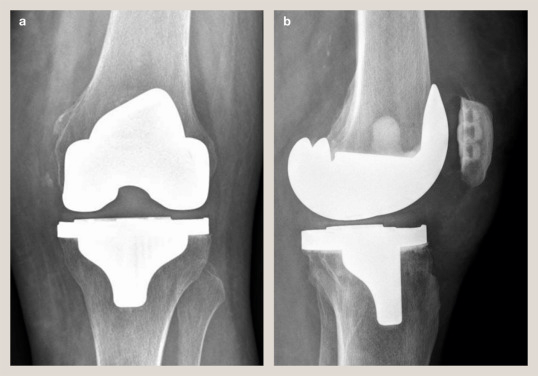

— Our Services

We Provide Exclusive Service

— Our Product

Take a Look at Our Awesome Gallery